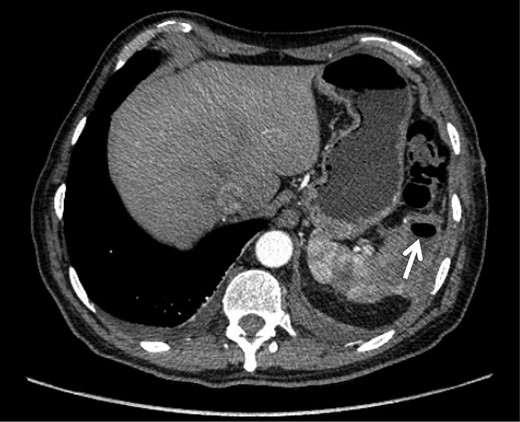

Intraoperative findings included extensive inflammation involving the inferior half of the spleen, the splenic flexure of the colon and the distal pancreas, as well as the abscess in question which contained approximately 10 cc of purulent material (Figs 3 and 4). The final surgical specimen included the entire spleen and the histologic report of pancreatic tissue compromised by the abscess. The patient was transferred to the surgical ICU for 24 hours. The following day, the blood cultures taken on admission grew an extended spectrum beta-lactamase producing Escherichia coli resistant to carbanemic agents and sensitive to tigecycline. The antibiotic regimen was modified accordingly, and after 7 days the patient was discharged symptom-free and with a plan to complete 15 days of tigecycline at home.

Inflammatory tissue dissection and drainage of the splenic abscess.